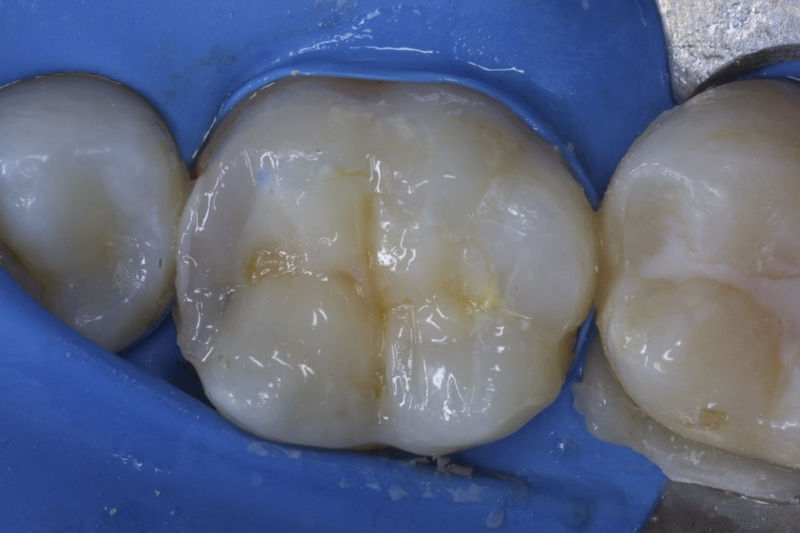

Restauraciones fabricadas en el laboratorio con materiales estéticos, los cuales cubren de manera parcial dientes posteriores. Se utilizan primariamente para restaurar dientes con caries, fracturas y/o defectos amplios. Para poder enviar el caso al laboratorio se toman impresiones utilizando materiales de impresión o técnicas modernas digitales.